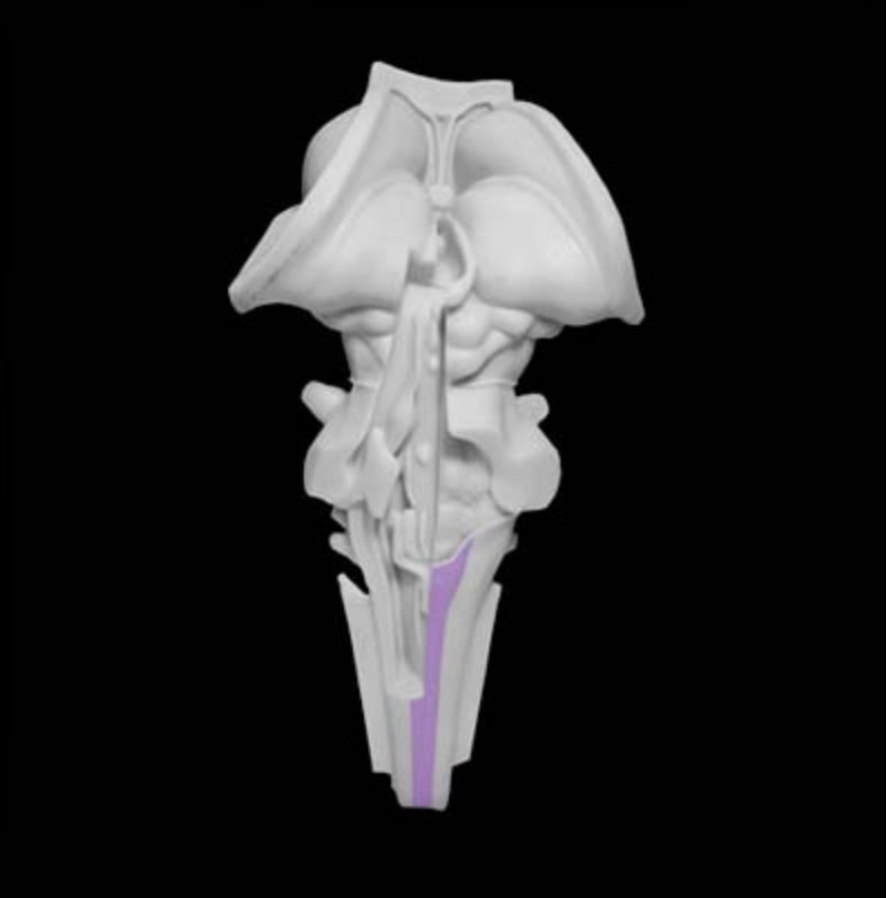

Pyramidal decussation

Prominent structure in the caudal medulla formed by the midline crossing (i.e., decussation) of corticospinal tract axons; the approximately 90% of the corticospinal tract axons that decussate in the caudal medulla then form the lateral corticospinal tract, and the 10% of the axons that do not cross the midline form the ventral (or anterior) corticospinal tract.